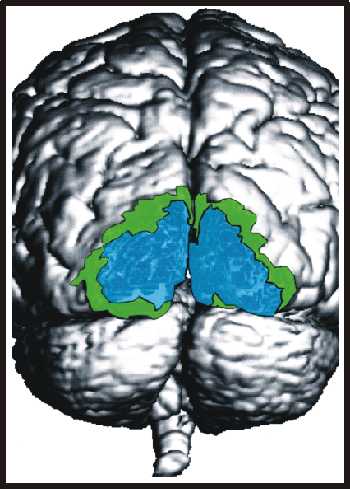

Die funktionellen Daten (bunt) in den beiden Bildern unten wurden mit der funktionellen Kernspintomographie (fNMR) gewonnen, bei der man Änderungen des NMR-Signals bei zunehmender Durchblutung eines aktiven Hirnareals auswertet. Als Beispiele für die Kombination von Bildern sind Überlagerungen von fNMR-Daten mit einem Kernspintomogramm (links) und mit einer graphischen Darstellung des Gehirns (rechts) abgebildet.

Aus: Forschen in Jülich, 1/2000, Forschungszentrum Jülich

fnmrh.jpg fnmr2h.jpg